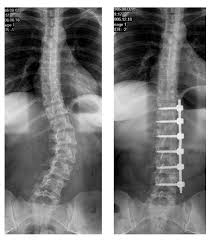

A későbbiekben, 20-22 éves korban, amikor a csontosodási folyamatok már befejeződtek, egy korábban kialakult súlyos esetben (lásd a fenti kép jobb oldalán lévő esetet) már nem sokat tehetnek.